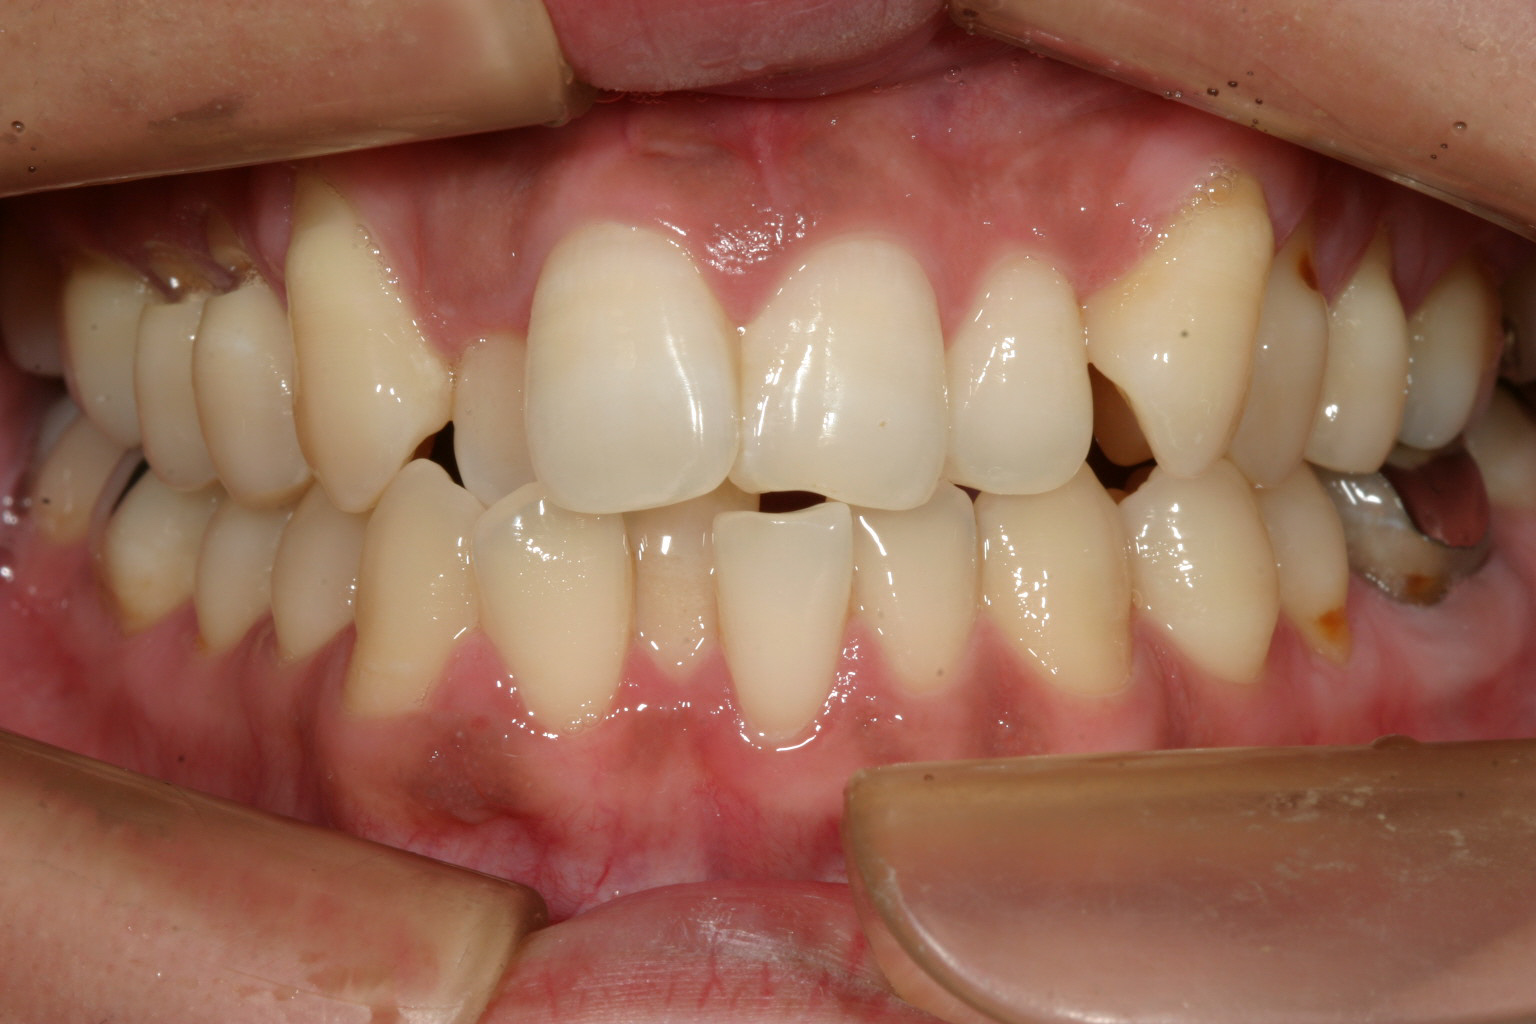

アーチがV字の為4本の前歯が並ばず叢生が激しいです。

上顎がV字型の為下顎もV次型でその為叢生が存在します。

上下叢生の為横から見てもガタガタしてます。